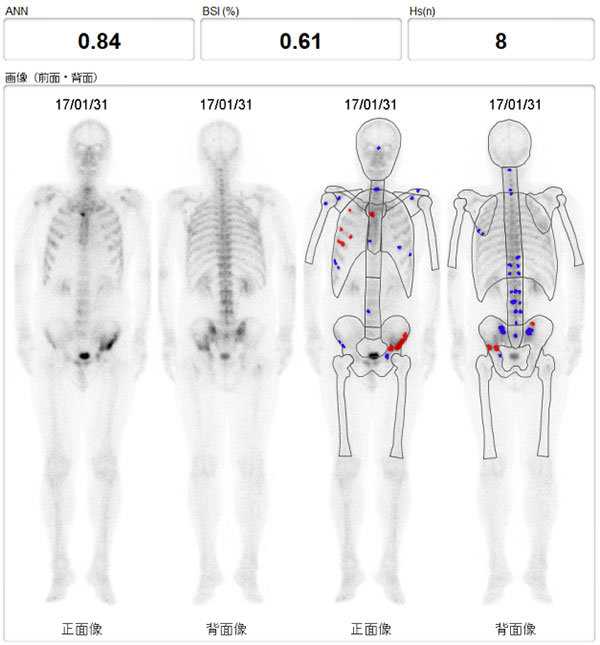

今年8月に前立腺癌の生検を受け10本中1本陽性でした グリソンスコア6psa155でした 9月骨シンチを受け1箇所集積があるとの事ただし1箇所である事と呼称は忘れましたがマーカーのような数字が0から1までの間で034と. 骨シンチ 40程に改善 足の痛み違和感ほぼ消える 身体に不都合何もなし 平成12年 4月 psa 05 骨シンチ 腰椎骨盤以外はほぼ消えた 左足は椅子に座っているとしびれの様なものを感じる程度 平成12年.

全身骨シンチグラフィ 乳癌 肺癌 前立腺癌等の骨転移病巣の検出

第15回日本核医学会春季大会ランチョンセミナー 骨転移の診断 治療

全身骨シンチグラフィ 乳癌 肺癌 前立腺癌等の骨転移病巣の検出

骨シンチグラフィによる骨転移の診断 Bone Scan Ct Mri画像診断